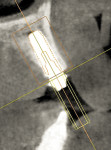

3D dentistry is truly transformative. By integrating computer-assisted implantology via GALILEOS® CBCT imaging (Dentsply Sirona Imaging, dentsplysirona.com) clinicians can confidently offer streamlined solutions for complex dental problems and provide advanced treatment options. Dentsply Sirona’s innovative SmartFix® concept affords implant dentists unique, reliable rehabilitation possibilities. The Astra Tech EV drilling protocol ensures primary stability for implant placement when immediately loading. Use of a digital workflow to diagnose and treatment plan removes guesswork, provides predictability, and ensures precision to return esthetics and function. The Profile EV implant, designed to follow the geometry of the alveolar ridge, decreases the need for bone reduction when tilting posterior fixtures by placing them at or slightly below the crestal bone. Restorative product options provide expanded choices with regard to angulations, tissue depths, and interocclusal spaces. Available prosthetic products simplify the restorative process for converting an immediate denture to an implant-retained fixed provisional prosthesis during the “teeth in a day” treatment procedure. As shown in this case, the patient gains expeditious improvement in esthetics, speech, and function with a single-staged, immediate-load, fixed hybrid prosthetic solution.

Combining the Profile EV implant with planning software and using surgical guide safeguards enables precise placements with improved control of depth, angulation, and timing. The SmartFix concept streamlines all-on-4 oral rehabilitation.